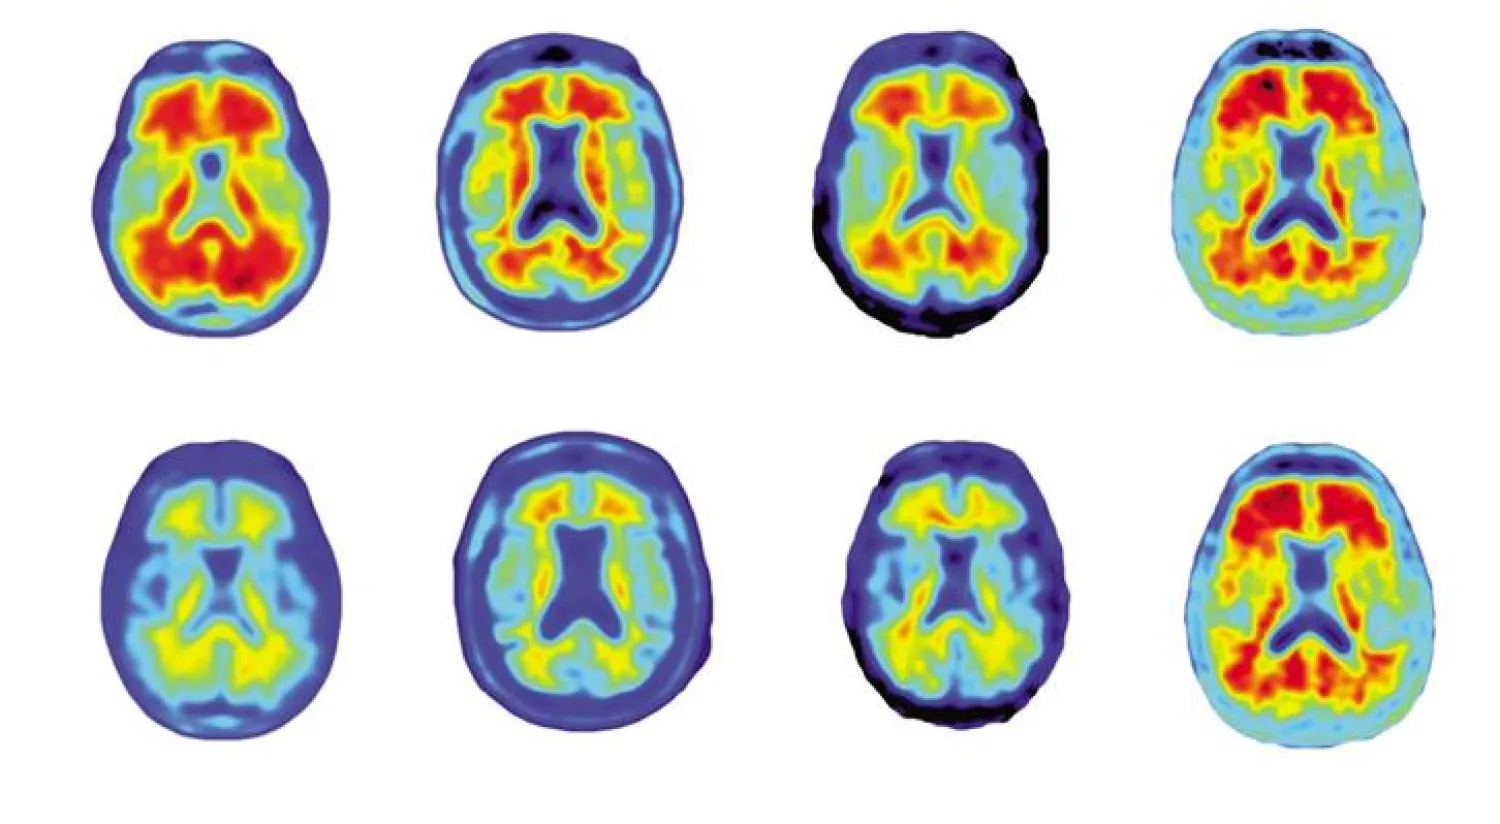

وفي خلال عام، سجل لدى المرضى الذين تناولوا جرعات أعلي من الدواء تراجع «ملحوظ» في لويحات الأميلويد في الدماغ، إضافة إلى توقف في تراجع قدراتهم الإدراكية، خلافا للذين تلقوا علاجا وهميا.

ويمثل تراكم أجزاء من بروتينات اميلويد - بيتا في الدماغ، التي تمنع التواصل الطبيعي بين الخلايا العصبية، إحدى علامات الإصابة بألزهايمر، وهو مرض انتكاسي دماغي مستعص يصيب أكثر من ثلاثين مليون شخص حول العالم.